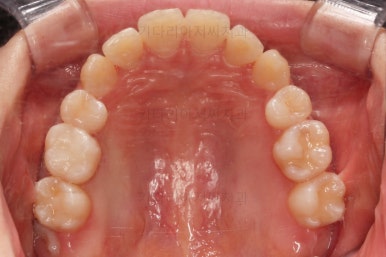

마찬가지로 초진 시 입안의 모습인데요.

전반적으로 약간 삐뚤지만 특히 윗니 앞니가 삐뚤고요.

송곳니는 덧니처럼 튀어나와 보이네요.

그리고 전반적으로 치아가 앞쪽으로 경사되어 있어서 앞니는 뻗친 느낌이 있네요.

가지런하게 하면서 앞니를 뒤로 당겨줘야 여러 가지 문제점들이 개선되기 때문에 발치교정을 했어요.